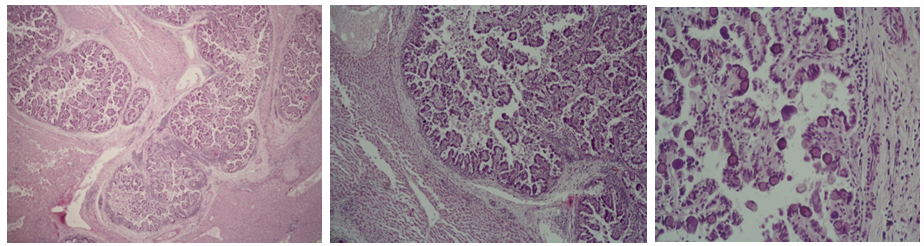

SCC (Canceroid- Squamous cell carcinoma)

Description: Cells resemble those of normal stratum spinosum, but have vesicular nuclei with one or more prominent nucleoli. We can observe eosinophilic stained formations growing into the dermis. Tumor cells spread throughout the dermis as slender anastomotic cords, with some cells falling off and remaining as isolated islands in the dermal stroma. Keratinization within islands results in laminated keratin pearls surrounded by tumor cells. At the periphery cells resemble basal cells following differentiated cells of stratum spinosum, and keratinization in the center.

Etiology: UV radiation (sunlight). Some breeds are more at risk than others.

Pathogenesis: Carcinomas are malignant epithelial neoplasms and SCC are tumors of squamous epithelium. They are common on eyelid and conjunctiva of cattle and horses, ear pinna of cats and sheep, vulva of cattle, goats and recently sheared sheep.